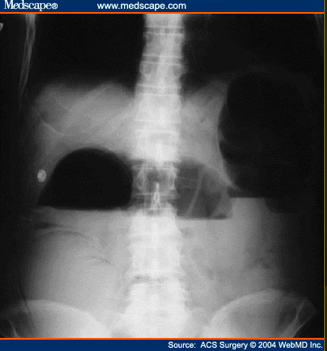

What type of bowel gas pattern?

Small Bowel Obstruction

What does this show?

complete small bowel obstruction showing multiple air-fluid levels of varying size arranged in inverted U’s.

What does this show?

distended small bowel loops

bowel wall b/w loops is thickened and edematous (large white arrow)

No air is seen in the colon or rectum